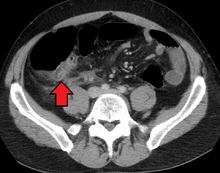

Computed tomography

Where it is readily available, computed tomography (CT) has become frequently used, especially in people whose diagnosis is not obvious on history and physical examination. Concerns about radiation tend to limit use of CT in pregnant women and children, especially with the increasingly widespread usage of MRI.[47][48]

The accurate diagnosis of appendicitis is multi-tiered, with the size of the appendix having the strongest positive predictive value, while indirect features can either increase or decrease sensitivity and specificity. A size of over 6 mm is both 95% sensitive and specific for appendicitis.[49]

However, because the appendix can be filled with fecal material, causing intraluminal distention, this criterion has shown limited utility in more recent meta analyses.[50] This is as opposed to ultrasound, in which the wall of the appendix can be more easily distinguished from intraluminal feces. In such scenarios, ancillary features such as increased wall enhancement as compared to adjacent bowel and inflammation of the surrounding fat, or fat stranding, can be supportive of the diagnosis, although their absence does not preclude it. In severe cases with perforation, an adjacent phlegmon or abscess can be seen. Dense fluid layering in the pelvis can also result, related to either pus or enteric spillage. When patients are thin or younger, the relative absence of fat can make the appendix and surrounding fat stranding difficult to see.[50]